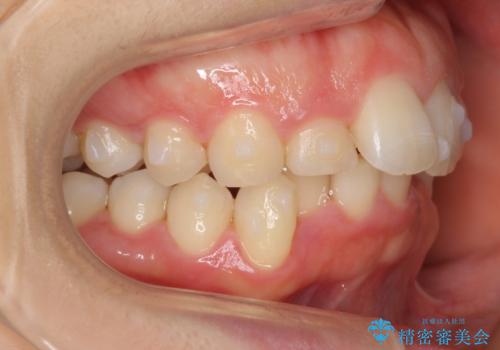

- 前歯のがたがたと出っ歯を主訴に来院。

CTを撮影したところ、臼歯部の頬側の骨の厚みが非常に大きく、通常では考えられない量の歯列の拡大が可能でした。

今回は健康を損なわずに非抜歯で治療が可能でしたが、

歯ぐきや骨の厚みが薄い他の患者さんでは難しいです。

左上5は180度捻転していましたので、そのまま並べています。

遠心移動などは行わず、IPRと拡大のみで治療を行いました。

一般的に非抜歯矯正を無理に行うと、口元がモッコリ出てしまうことがあります。しかし、今回は前歯を前に出さないような設定にしており、口元が出ることもありませんでした。